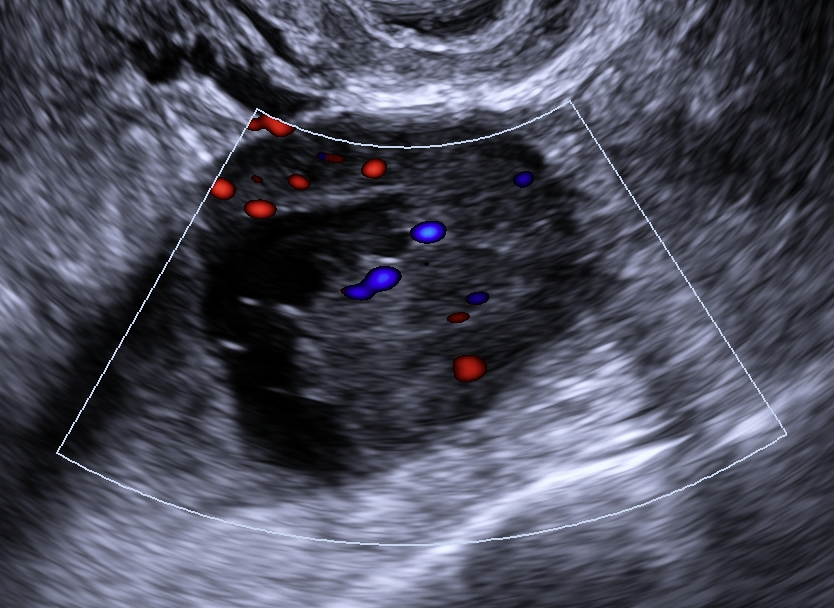

O sistema O-RADS US (Ovarian-Adnexal Reporting and Data System Ultrassonografia) é um sistema de classificação de risco padronizado para massas anexiais baseado em características ultrassonográficas.

Risco: ≥50%Cisto unilocular com ≥ 4 projeções papilares, cisto multilocular com componente sólido e IC = 3–4, lesão sólida com IC = 4 ou superfície irregular, presença de ascite e/ou nódulos peritoneais.